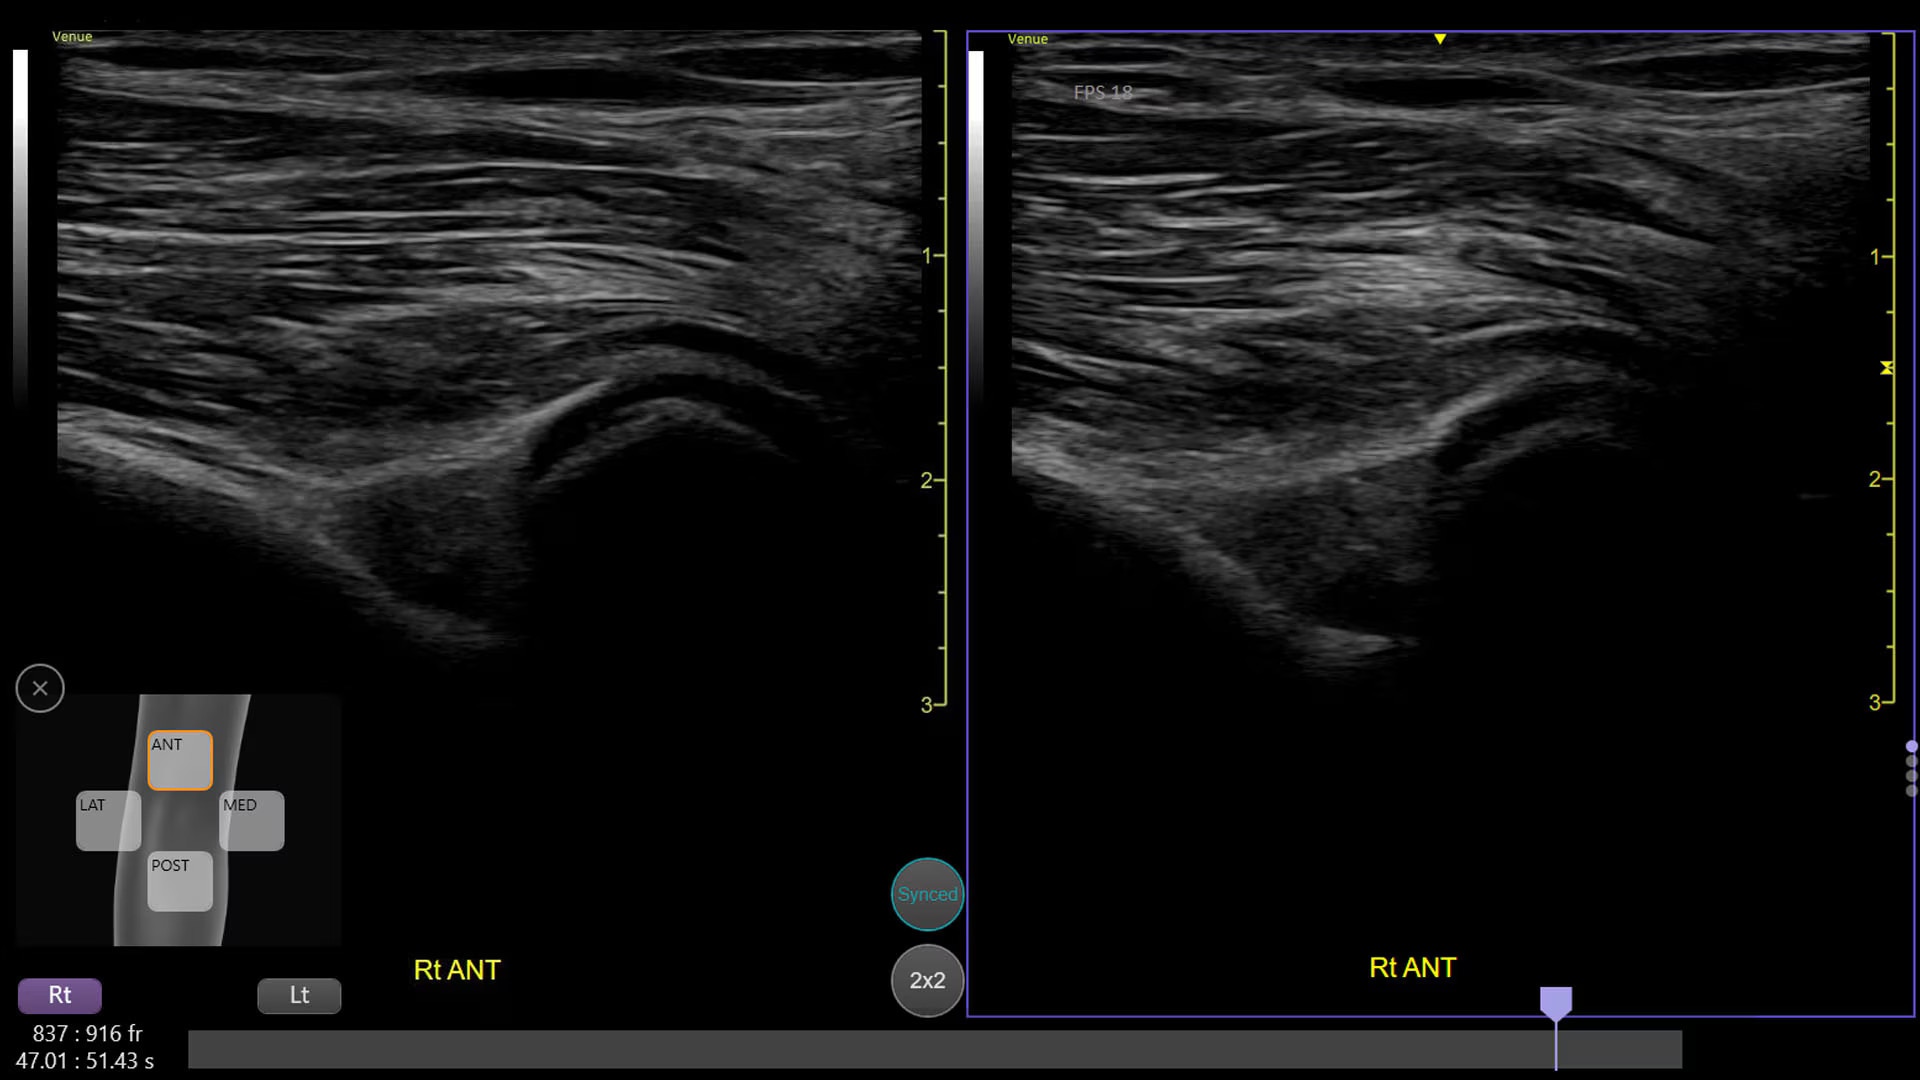

Automated tools

Simplify your workflow with AI-enabled clinical tools.

Helping drive consistency from user to user (whether one is an ultrasound novice or expert), Venue Fit features AI-enabled resources that help clinicians work smarter and more efficiently. Utilizing proprietary algorithms, we synthesize data from numerous patients to ensure accurate calculations for clinical confidence.